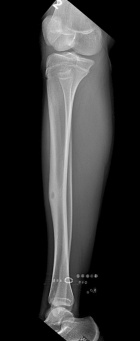

15 yo female with 8 mo h/o aching, right anterior leg pain. C/o of pain at night and with activity alleviated w/ rest and ibuprofen. She denies h/o trauma or constitutional symptoms.

PE: Bony prominence at right anterior tibia w/o notable edema or erythema. Full ROM at knee. NVI. No LAN.